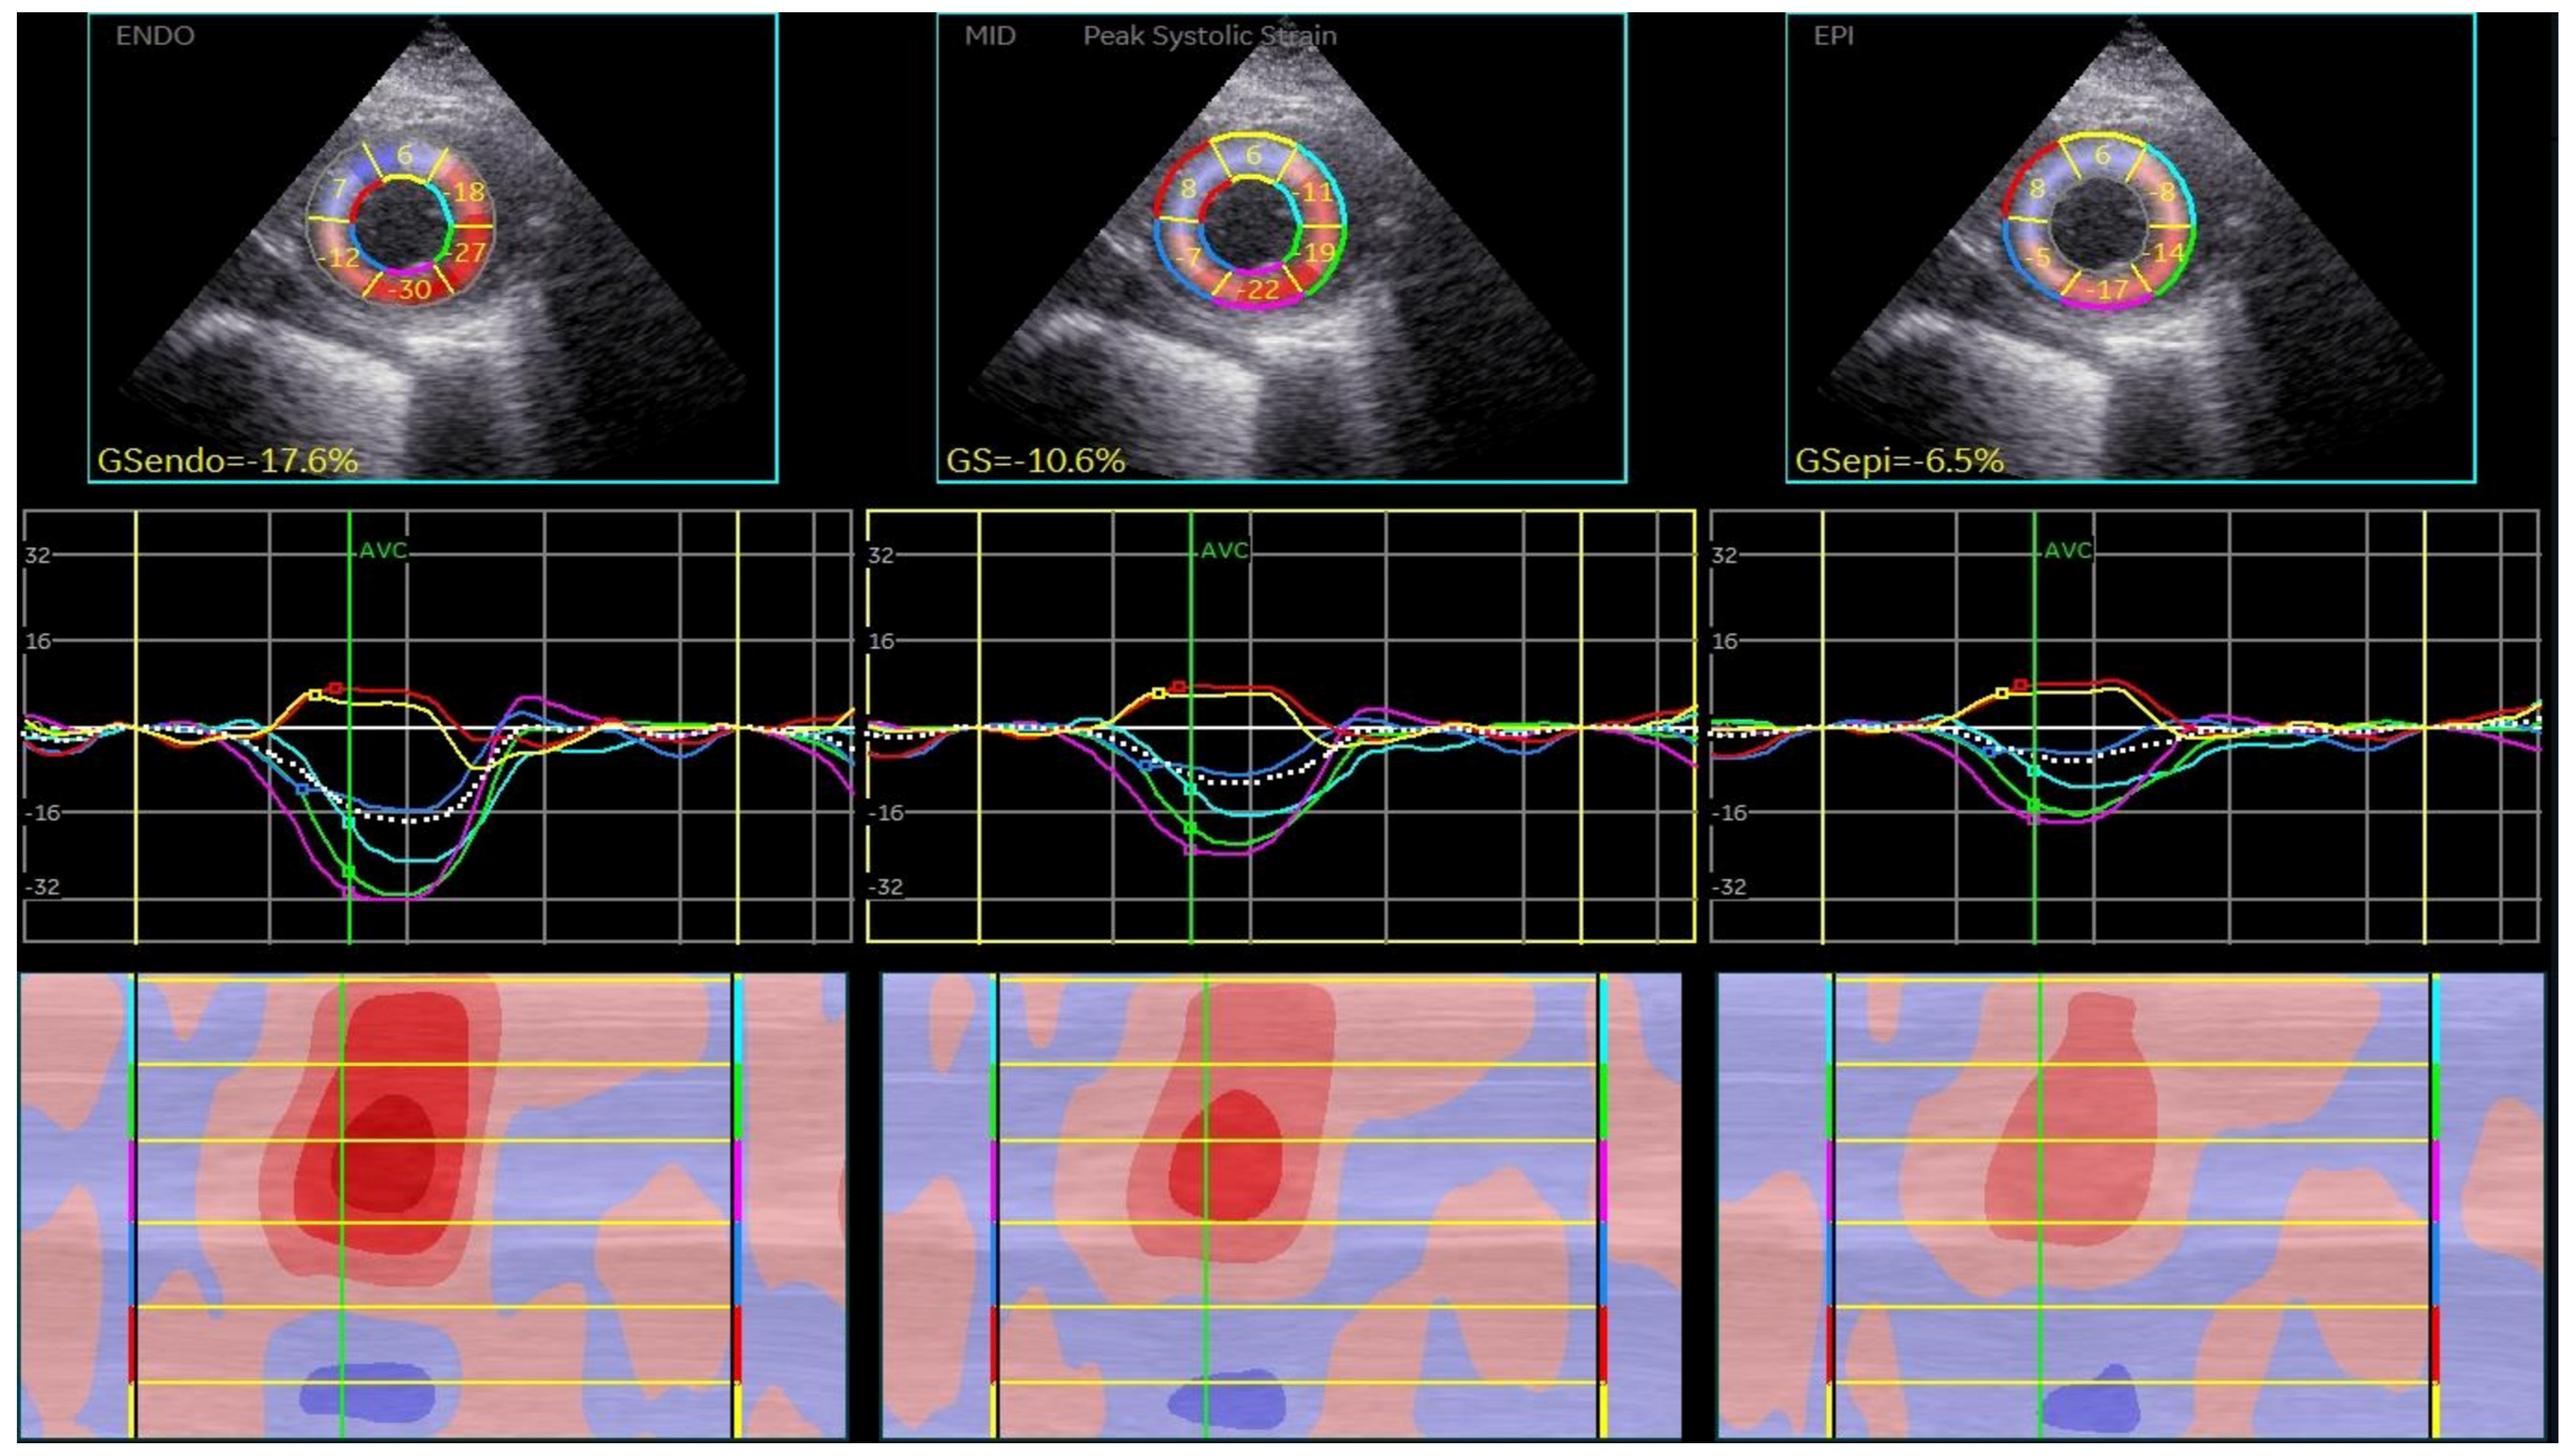

2.2.2. Two-Dimensional Speckle-Tracking Echocardiography

3.2. 2D Speckle-Tracking Echocardiography Results